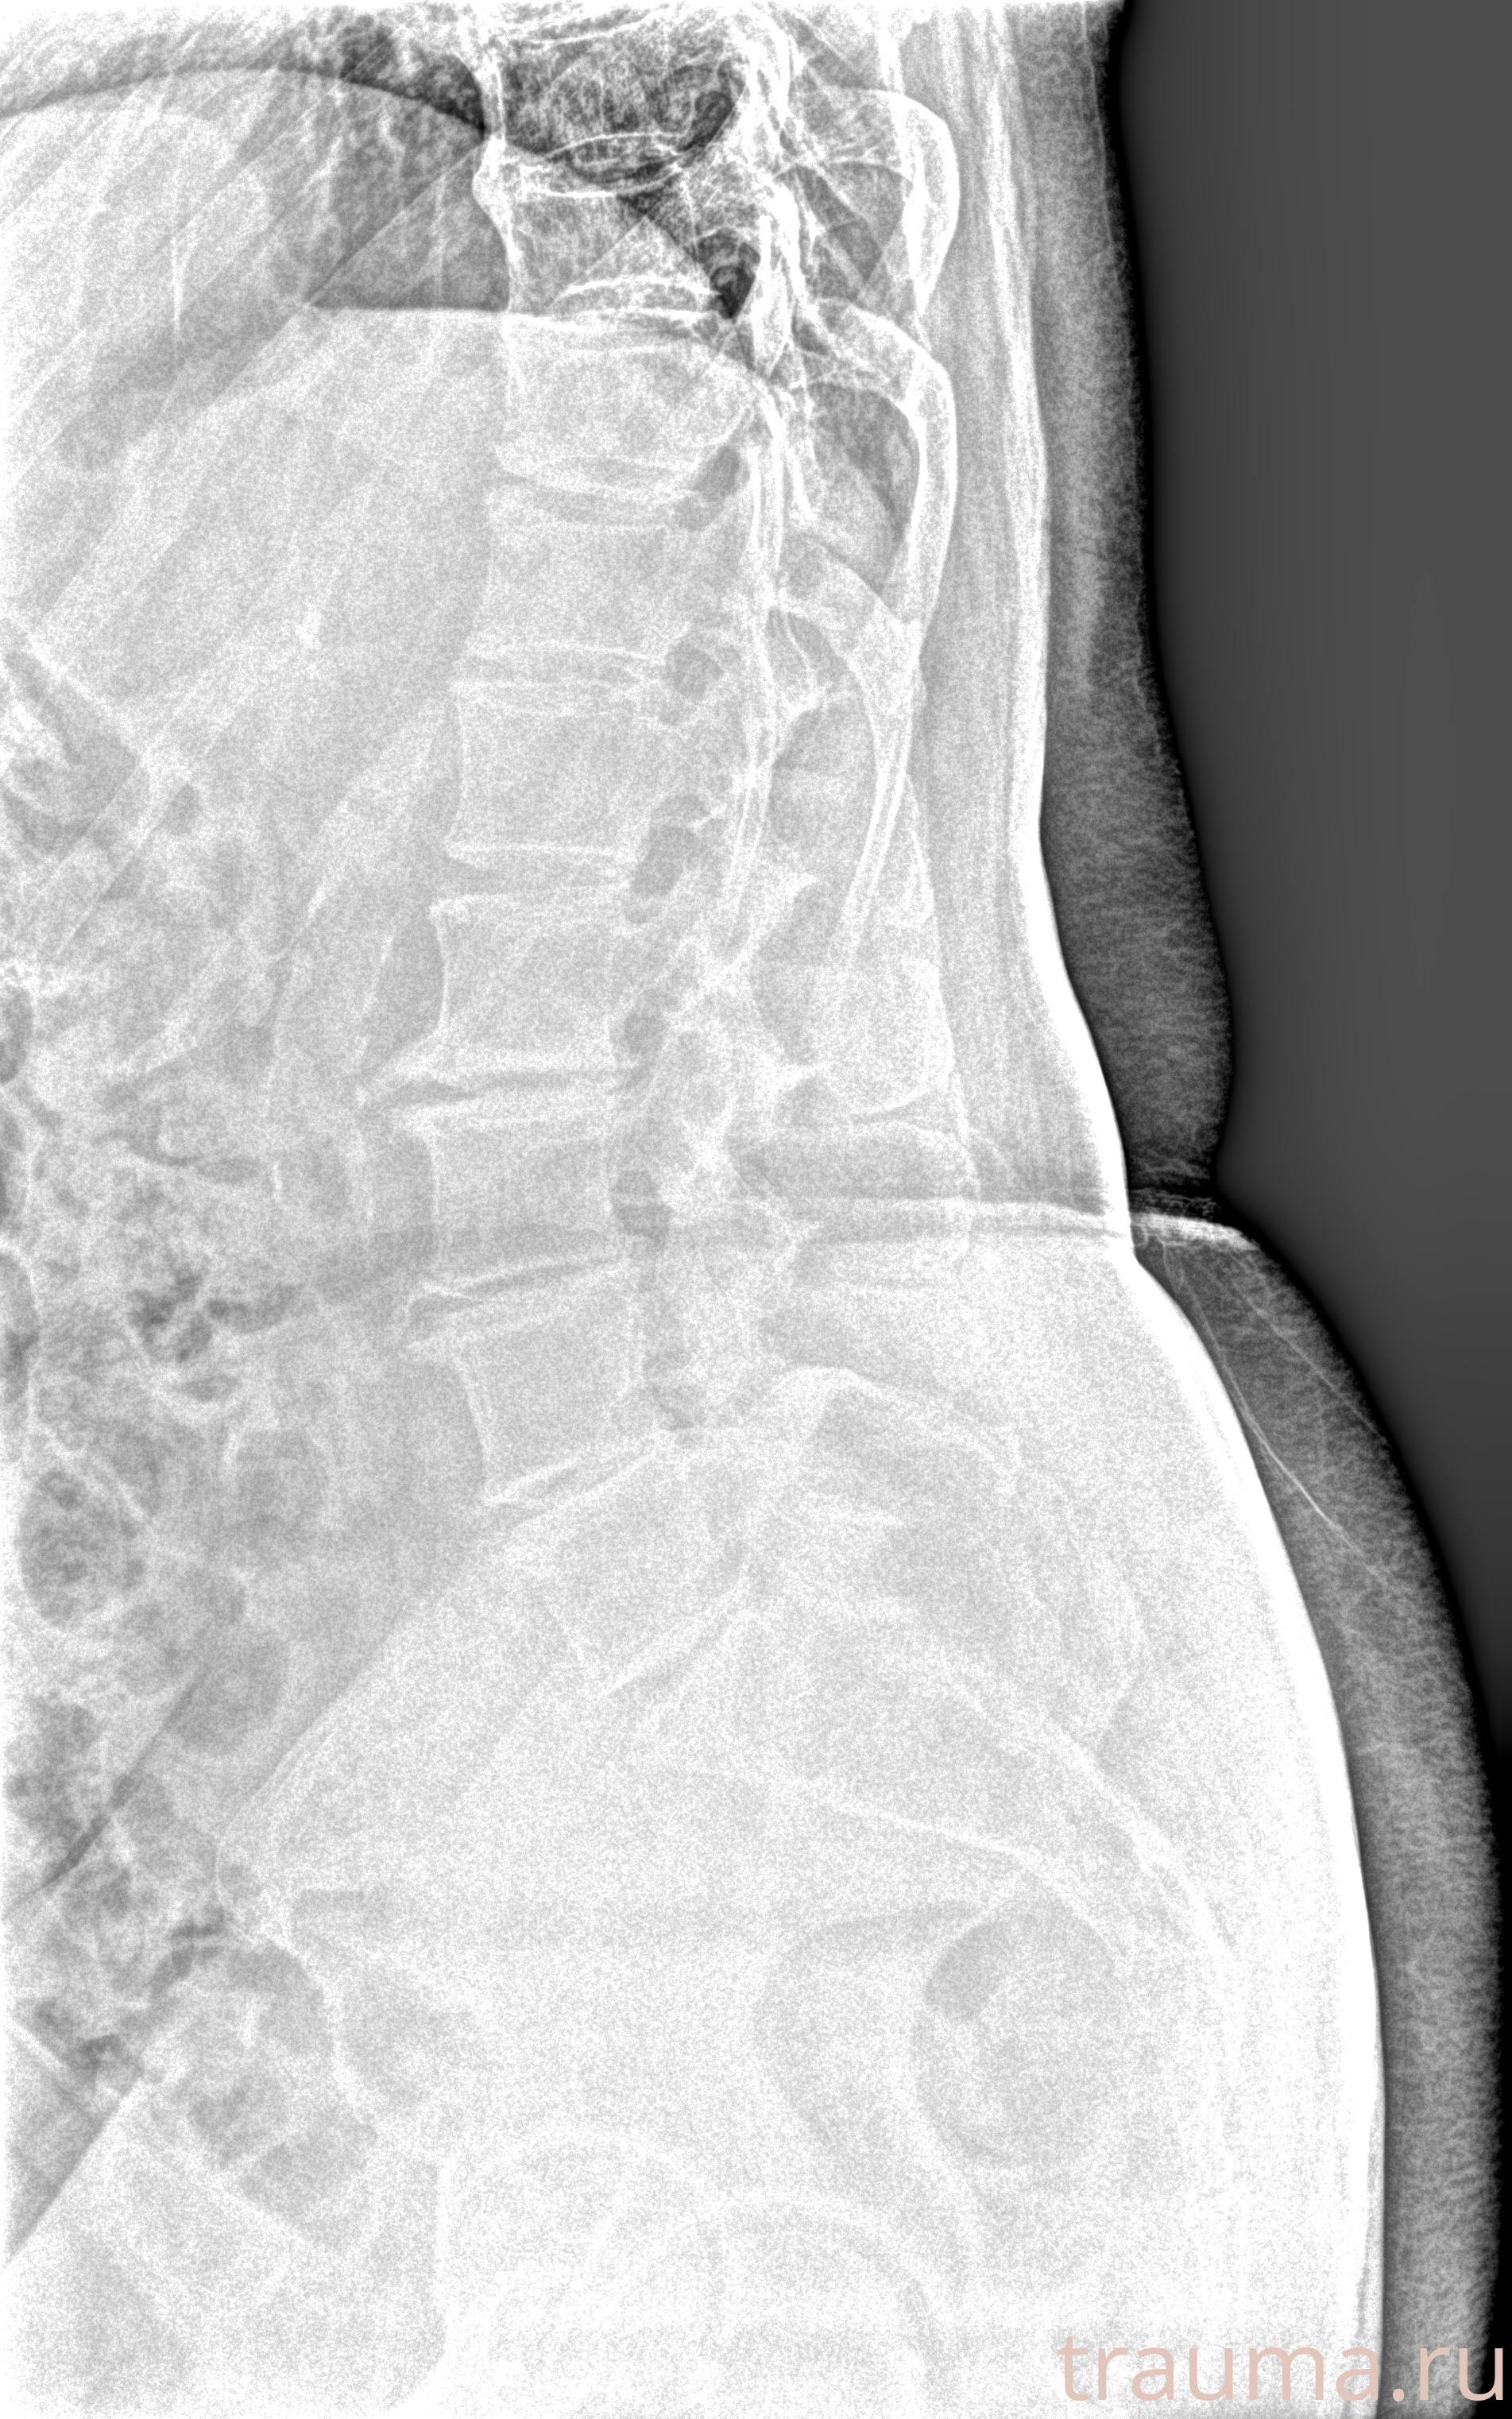

Рентген на дому: по вашему адресу приезжает врач-рентгенолог, травматолог-ортопед с мобильным рентгеновским аппаратом, проводит диагностику травмы или заболевания, делает необходимые рентгенограммы, дает рекомендации по дальнейшему лечению. Получить качественные снимки в домашних условиях возможно благодаря уникальной методике, разработанной МосРентген Центром для института  Склифосовского